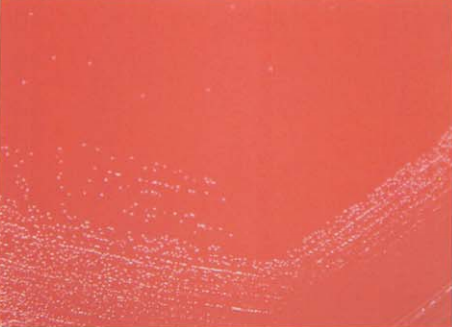

(二) 溶血孪生球菌培养特性

在血琼脂平板上35℃培养18~24 h,形成细小、凸起、光滑、有β溶血的菌落(图 4),与溶血性链球菌很相似,某些菌株可产生α溶血或不溶血。

图 4 溶血李生球菌在血琼脂平板上的菌落特征(18~24h)